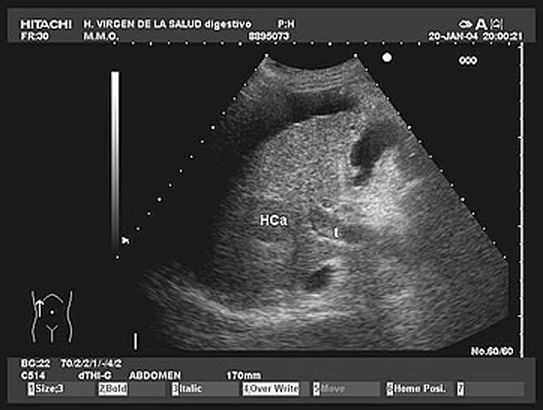

1.5. Anomalías vasculares